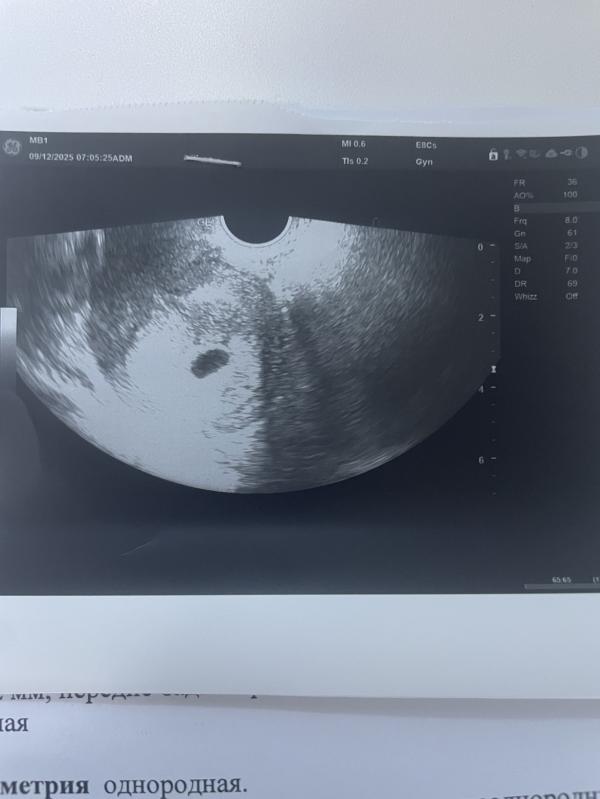

Девочки,ПЯ растет,но внутри пусто,врач сказала ждем неделю,у кого может было так,хочу послушать…

Ну я верю в малыша,еще думаю,что могли плохо посмотреть-смотрела от силы 5 минут

@akatya26, ну вот и я хочу сходить платно на УЗИ,тут вроде немецкое хорошее оборудование,но оно старое,может и не видно было поэтому